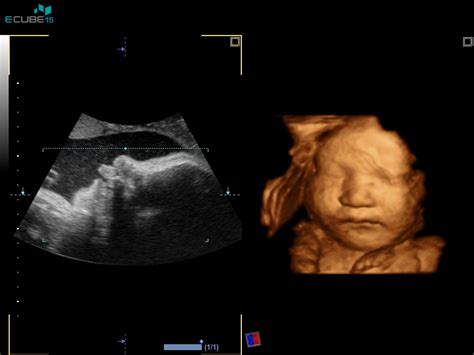

V 7. tednu nosečnosti vaš otrok meri med 4 mm in 10 mm ter je velik približno kot borovnica. Na tej stopnji dojenčkova glava raste hitreje kot telo, kar je odraz hitre in intenzivne rasti možganov. Razvija se tudi srce, ki je že razdeljeno na desni in levi prekat. Če bi lahko videli obraz svojega otroka, bi lahko že opazili dve majhni nosnici. Oblikujejo se tudi usta, nastajajo ustnice, jezik in zametki zob.

Do konca tega tedna bo dojenček več kot polovico večji kot prejšnji teden in bo dosegel dolžino od 11 do 13 milimetrov, kar ga približa velikosti maline. Njegova glava je nesorazmerno večja od ostalega dela telesa, temne pike pa označujejo, kje bodo njegove oči in nosnice. Zasnove dojenčkovih rok se že delijo na ramena, komolca in dlani. Sedaj bi vas verjetno bolj spominjale na mala vesla, saj prstki še niso izoblikovani. Tudi njegov obraz dobiva obliko. Opazna je že obarvanost šarenice in majhna usteca.

V tem tednu se pričnejo iz okončin razvijati roke in stopala, ki so videti kot lopate, saj je velikost v primerjavi z okončinami nesorazmerna. Še vedno govorimo o zarodku, ki ima majhen rep. Le-ta bo izginil v nekaj tednih, do takrat pa bo postajal vse manjši in manjši. Če bi lahko videli v notranjost maternice bi opazili veke, pa tudi konico nosu in majhne žile pod pergamentno tanko kožo. Obe hemisferi možganov zarodka rasteta, jetra pa proizvajajo rdeče krvne celice, dokler se ne razvije kostni mozeg, ki bo kasneje prevzel to vlogo. Razvila sta se tudi slepič in trebušna slinavka, ki bo sčasoma pričela proizvajati hormon inzulin za pomoč pri prebavi.

Če še niste obiskali zdravnika, se dogovorite za termin, da lahko začne načrtovati vaše predporodno varstvo, vključno s prvim ultrazvočnim pregledom. Če tega še niste storili, boste šli ta teden verjetno na svoj prvi pregled. Zdravnik se bo z vami pogovoril o prejšnjih boleznih, nosečnostih ali genskih napakah, ki ste jih morda podedovali. Določil bo tudi predvideni datum vašega poroda in začel spremljati, koliko teže boste med nosečnostjo pridobili.